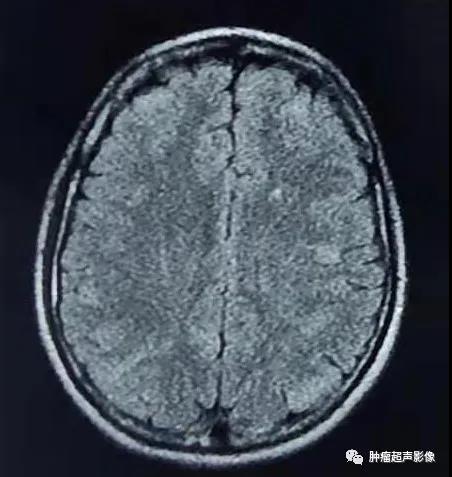

MR表现为两侧额枕叶皮层及皮层下多发结节或皮层增厚、脑回肥厚,FLAIR信号增高。

头颅CT示两侧侧脑室下多发小结节状钙化,增强MR示室管膜下结节明显强化。